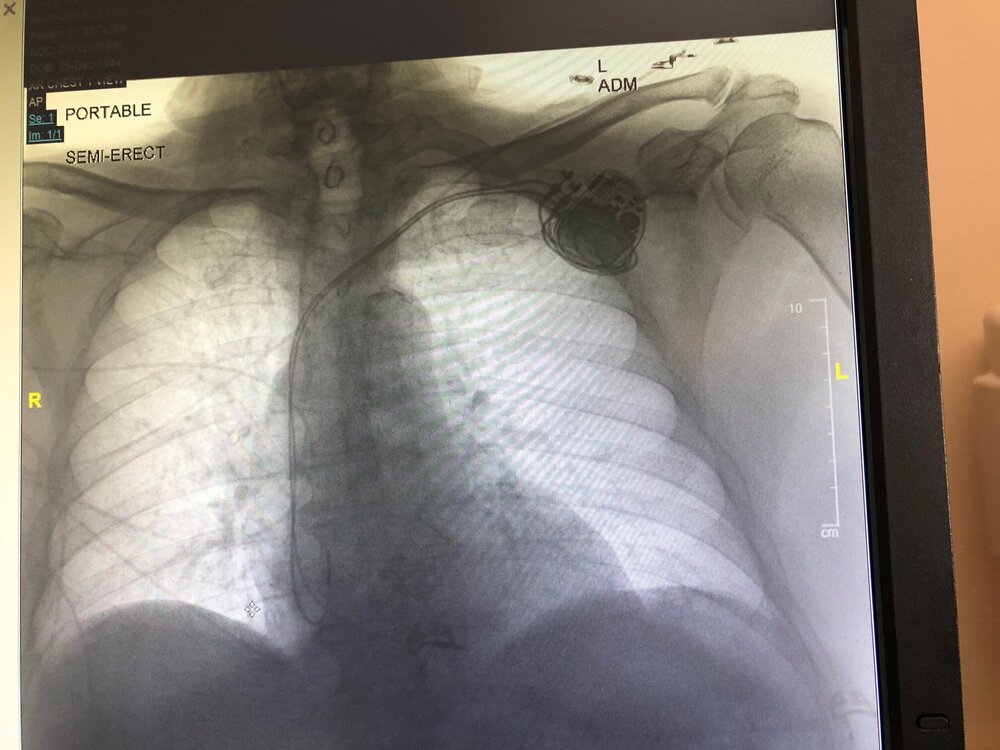

Yep -caused by some small blood clots on the lung -BS&W ER ran a bunch of scans & tests.

Didn’t sleep a wink in the ER last night. Just got in a regular room today.

7 or 8 cardiologists checked me out - new meds are clearing out the clots and I feel fine.

However the electro-cardiologist team & my main cardio doc said I need a pacemaker.

They’ll install it Friday.

SEMI-ERECT brings out my inner Beavis & ButtHead...

Nice Left Bundle Branch placement in the RV, should give you a nice, narrow QRS when V paced!

That’s exactly what I was thinking!